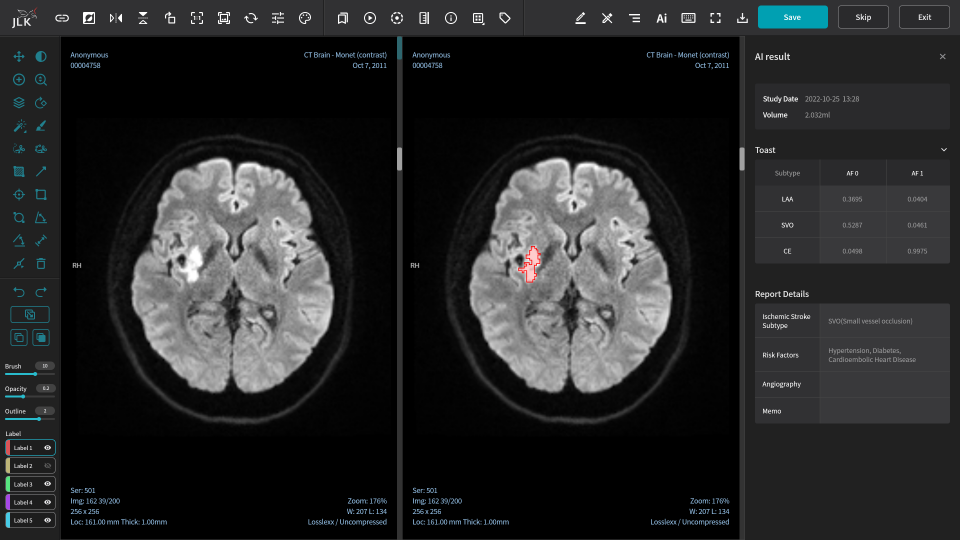

| 제이엘케이의 뇌경색 진단 솔루션 'JBS-01K'. /자료=제이엘케이 |

규제 개선으로 인한 성과는 올해부터 나타나고 있다. 제이엘케이의 뇌경색 진단 솔루션 'JBS-01K'는 지난해 12월 통합심사·평가 혁신의료기기 1호로 선정됐다. 이에 올해부터 비급여 보험 수가 적용이 가능해지면서 본격적인 수익화가 가능해진 상황이다.

규제 개선으로 인한 성과는 올해부터 나타나고 있다. 제이엘케이의 뇌경색 진단 솔루션 'JBS-01K'는 지난해 12월 통합심사·평가 혁신의료기기 1호로 선정됐다. 이에 올해부터 비급여 보험 수가 적용이 가능해지면서 본격적인 수익화가 가능해진 상황이다.